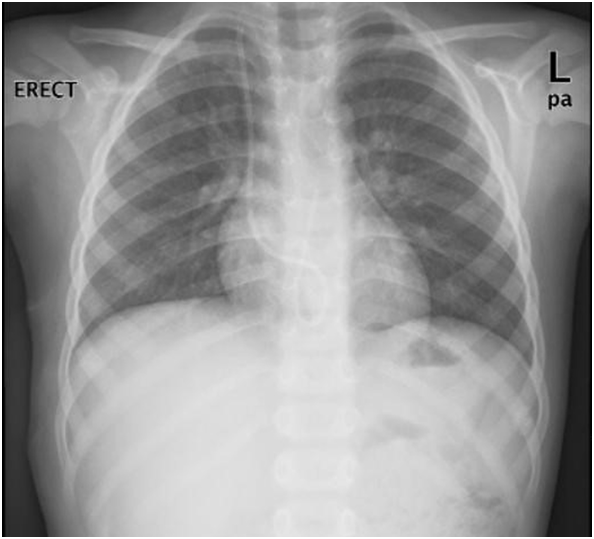

The Port-A-Cath was snared by 15mm loop (AMPLATZ GOOSE NECK). The snared Port-A-Cath could not be pulled into the MPA2 catheter. Consequently, both MPA2 catheter and snared Port-A-Cath were pulled through outside the heart with tight control on the snare to prevent it from slipping (Figure 6). There was no encountered resistance while pulling the Port-A-Cath, with stable hemodynamics. The child was extubated in the cardiac catheterization laboratory and recovered well from the procedure. A cardiothoracic surgeon has attended the operative theatre in case of any possible complication.

Figure 6 Shows removal of the catheter by loop-snare technique.